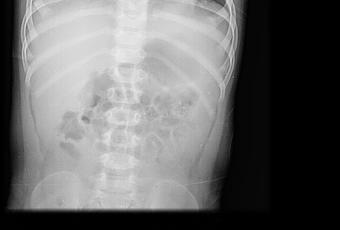

TÓRAX AP Y LATERAL

EN LAS PROYECCIÓNES RADIOGRÁFICAS OBTENIDAS MUESTRAN LOS SIGUIENTES HALLAZGOS:

Campos pulmonares, con presencia de imágenes que simulan ser micronódulos, de distribución Perihiliar.

IMPRESIÓN DIAGNOSTICA:

EN EL PRESENTE ESTUDIO RADIOGRÁFICO, CON IMÁGENES SUGERENTE DE BRONQUIOLITIS.